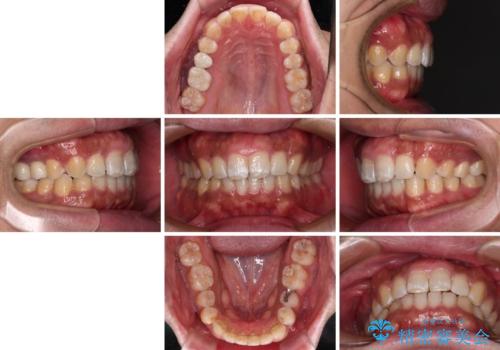

破折して抜歯が必要となった歯の後ろの歯は、根管治療が必要な状態であったので、根管治療を行い、矯正治療後にインプラント部の補綴治療と同時にセラミッククラウンを装着しました。

矯正治療以外に費用負担がかかることになりましたが、気になるところ全てを処置することができ、患者様には大変満足していただきました。